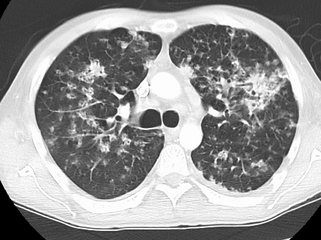

CT, showing extensive pulmonary parenchymal involvement consisting of irregular septal thickenings with ground-glass areas and centrilobular nodules with a peri-lymphatic distribution